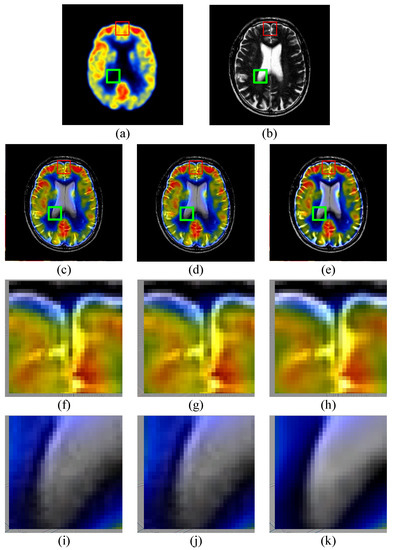

3.2.2. Medical Comparison